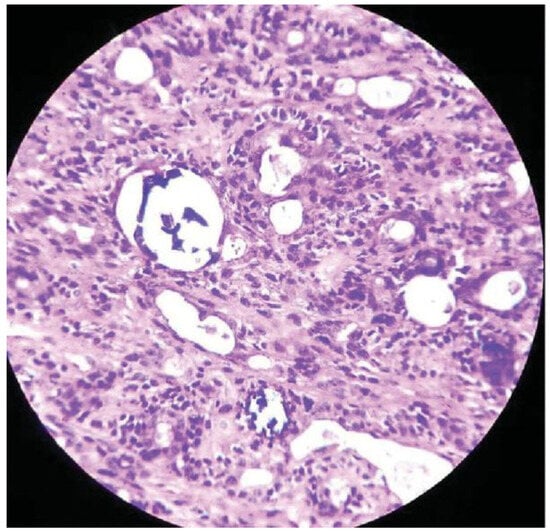

Basal Cell Adenoma of Retromolar Region from Minor Salivary Gland Origin in a 45-Year-Old Female: A Case Report

:Case Presentation